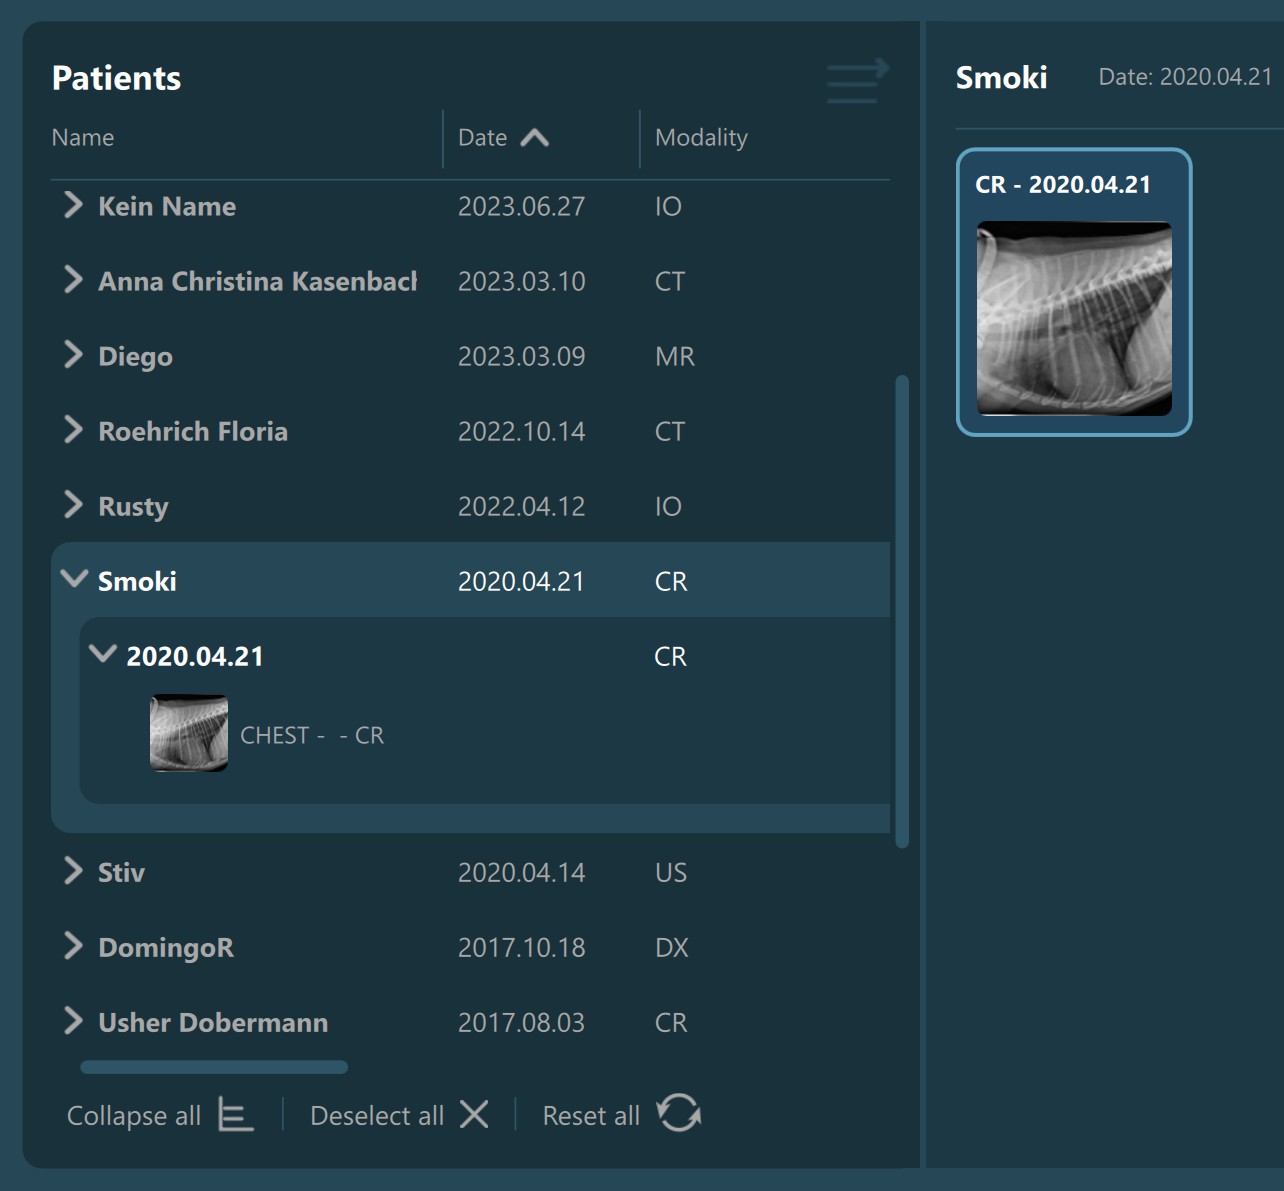

The Study List is located on the left side of the Study Browser window. All studies or patients (depending on the active mode) from the selected server will be displayed in the study list, based on the configuration of the DICOM servers.

Expand an item in the Study List by pressing the arrow next to the its name, which reveals its contents based on the DICOM hierarchy in the Study Browser.

Preview Pane¶

Selecting a patient, study, or series from the Study List opens them and their contents in the Preview Pane, located on the right side of the Study Browser window. In the Preview Pane, the items are separated into sections based on their patient information.

The heading of each section shows the patient name, the latest related study date, patient sex, and owner name. Studies are shown as image groups containing the series as image previews. Each study is highlighted by its modality and date. To view the series description of each series, hover over the desired image preview.

Similar to the selection in the Study List, users have the ability to select patients, studies, or individual series. A highlighted selection in the Preview Pane indicates the active selection in the Study List.

The Preview Pane can also be used to extend or narrow down the selection from the Study List. To select/deselect items in the Preview Pane simply press on them with the mouse.